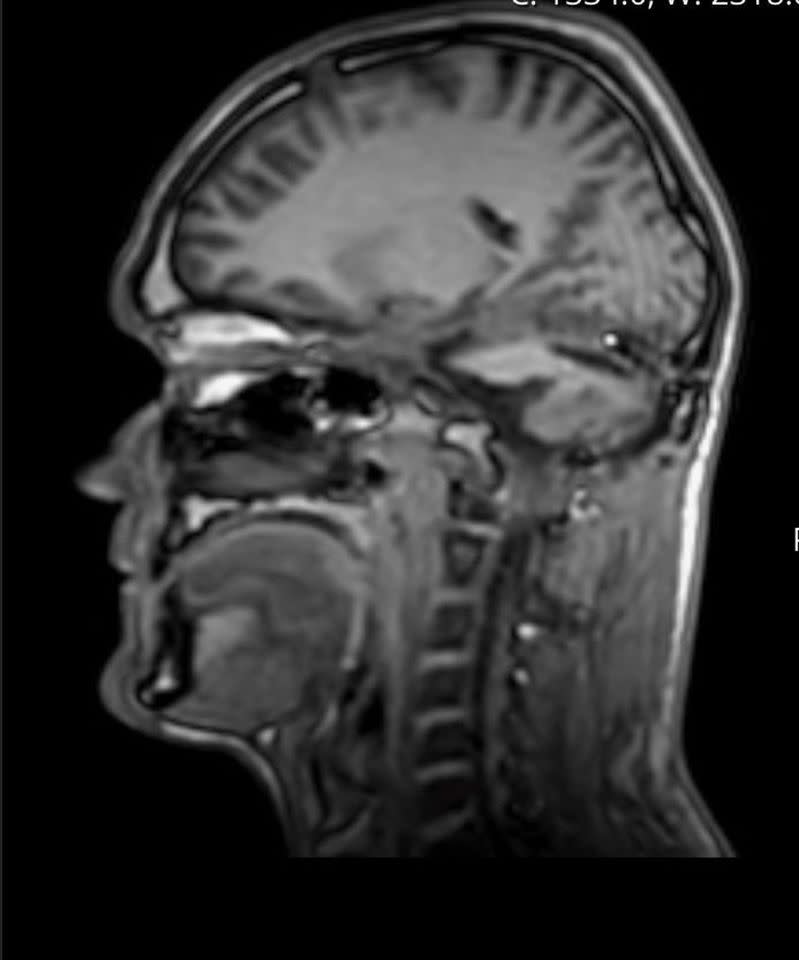

Luke Taylor’s brain scan

Credit: Nia Jones via SWNS

When the scans came back, Taylor was diagnosed with a haemangioblastoma, a rare benign brain tumor typically found in the cerebellum, which is essential for motor control and cognitive function.